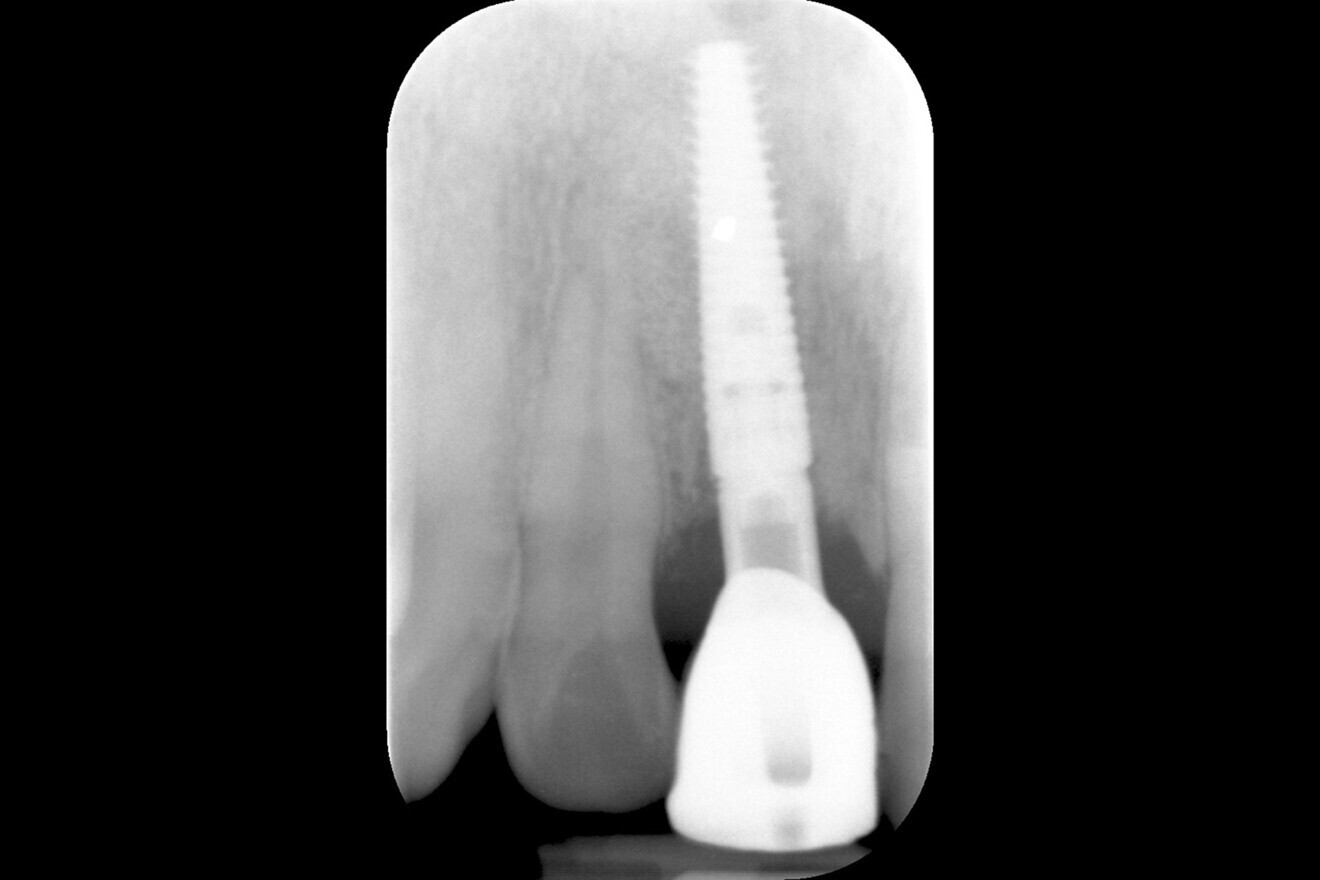

Fig. 13: Radiograph of the implant at baseline insertion of the definitive crown.